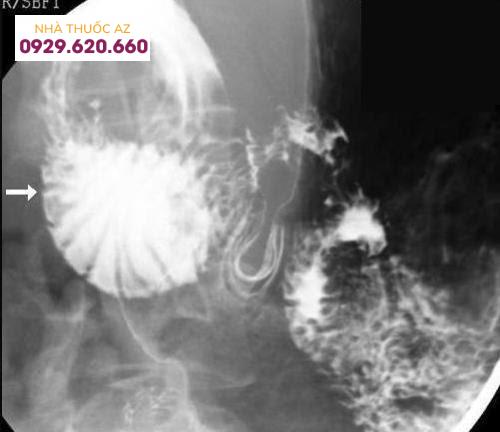

Tá tràng bị giãn rộng (mũi tên), bị thắt đột ngột bởi động mạch mạc treo tràng trên.

Soi và chụp tá tràng có cản quang ghi nhận: Dãn tá tràng D1 và D2. Chèn ép từ bên ngoài vào tá tràng D3. Tăng nhu động đoạn trên bị chèn ép và lưu thông từ dạ dày xuống tá tràng chậm. Giảm sự tắc nghẽn khi thay đổi tư thế.